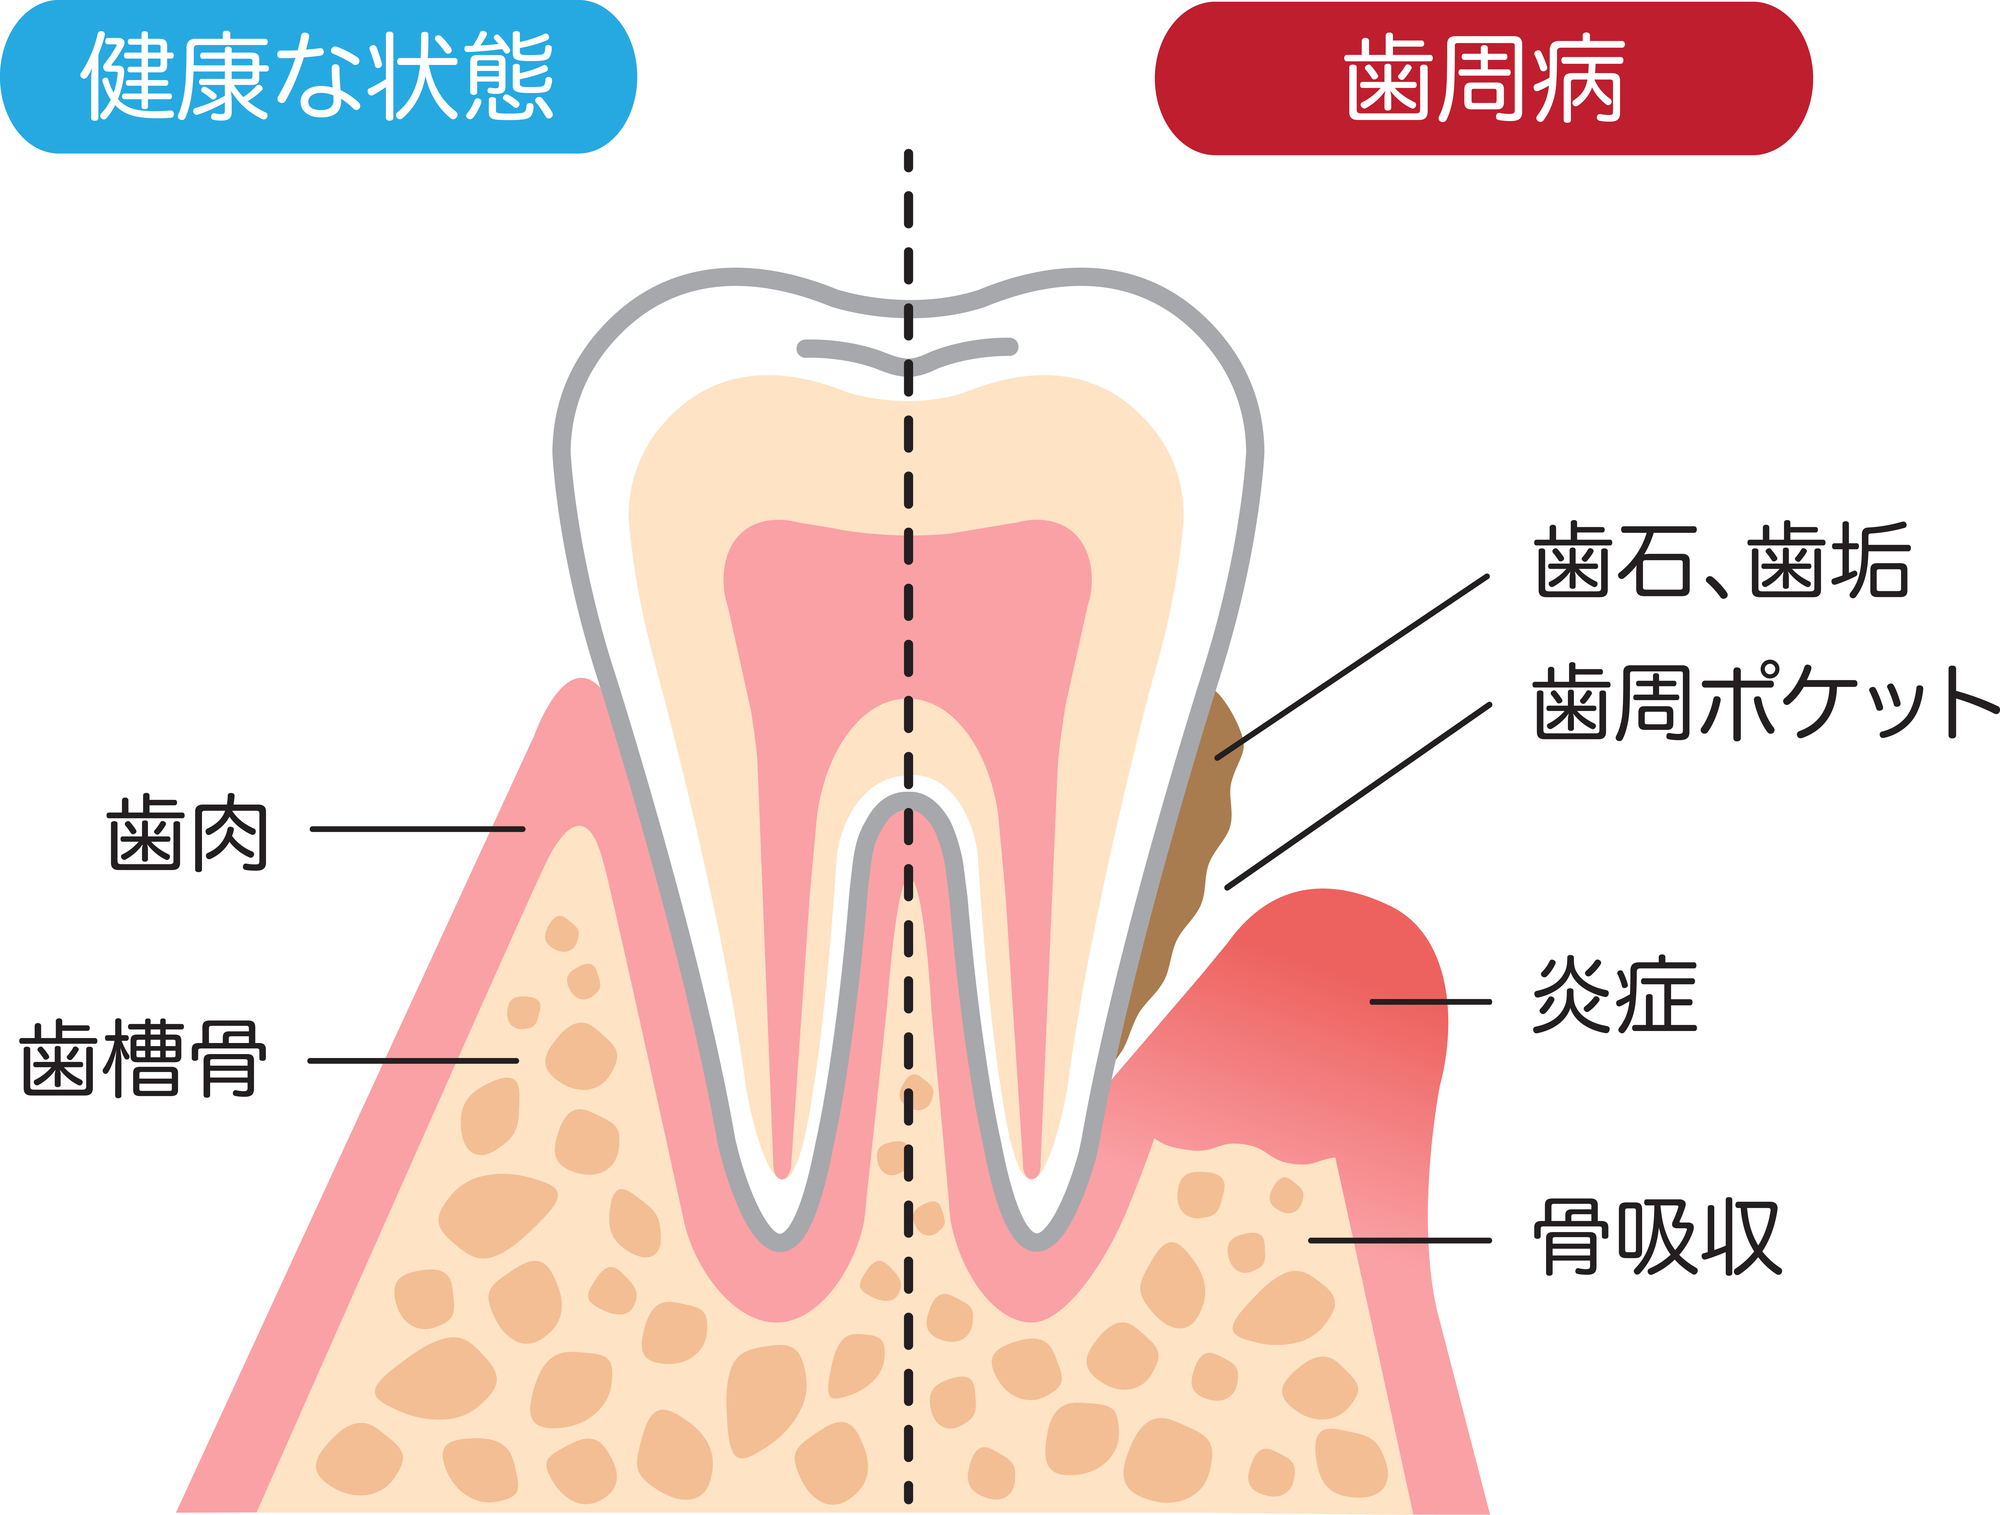

⑤歯周病が原因の場合

歯周病は歯ぐきの炎症だけではなく、歯を支えている顎の骨も溶かしてしまう病気です。骨に支えられている土台の部分が緩んでしまうため、進行すると歯が揺れ始めたり、歯並びが崩れやすくなります。この時に歯と歯の間に隙間が生じ、すきっ歯になってしまうことがあります。

すきっ歯は通常の歯並びと比べて、歯と歯の間の面が広くなります。そのため、歯磨きも難しくなりがちです。また食べかすが詰まったり残ったりしやすいので、虫歯や歯周病のリスクも高まります。

歯周病を予防する

歯周病にならないように、日頃から念入りなセルフケアと定期的な歯科医院でのメンテナンスを受けることを習慣にしましょう。